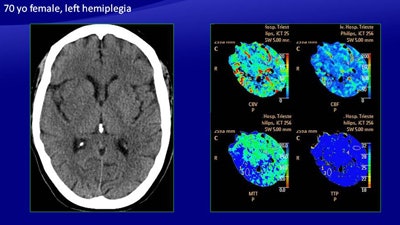

In the study, 26 patients with ischemic stroke underwent perfusion imaging in addition to noncontrast CT. Perfusion and core maps were automatically generated, along with separate evaluation of cerebral blood flow (CBF), cerebral blood volume (CBV), and mean transit time (MTT). The results showed that the manually generated maps were at least 10% more accurate than automatically derived maps, the researchers from Trieste, Italy, found.

"Analysis of the manually generated maps had greater sensitivity in comparison with the maps generated by the software, in particular in the infratentorial area and in the basal ganglia area [where] it tends to underestimate the extent of perfusion" said Dr. Maja Ukmar from the department of radiology at the University of Trieste.

Manual image processing was used to generate perfusion maps, followed by the software maps, "in which the green area meets the criteria for penumbra, and the red area meets the criteria for the infarct core," Ukmar said.

Among the manually generated maps, five had no perfusion abnormalities (two true negatives, three false negatives), while 14 showed perfusion abnormalities. There were 29 areas of perfusion deficit, including 15 compatible with ischemic penumbra and 14 with infarcted tissue, with a total of 14 true-positive cases on the manually generated maps.

For the manually generated maps, sensitivity was 82.3%, positive predictive value was 100%, specificity was 100%, and negative predictive value was 40%.

Among the ischemic penumbra results, one true positive on CBV analysis was a false negative on the automatically generated map, representing a large ischemic penumbra of the parietal lobe, adjacent to a large stroke.

The automatically generated maps had lower sensitivity than the manually generated ones, particularly in the infratentorial area and the basal ganglia area. The automated scheme also tends to underestimate the extent of perfusion of the ischemic penumbra.